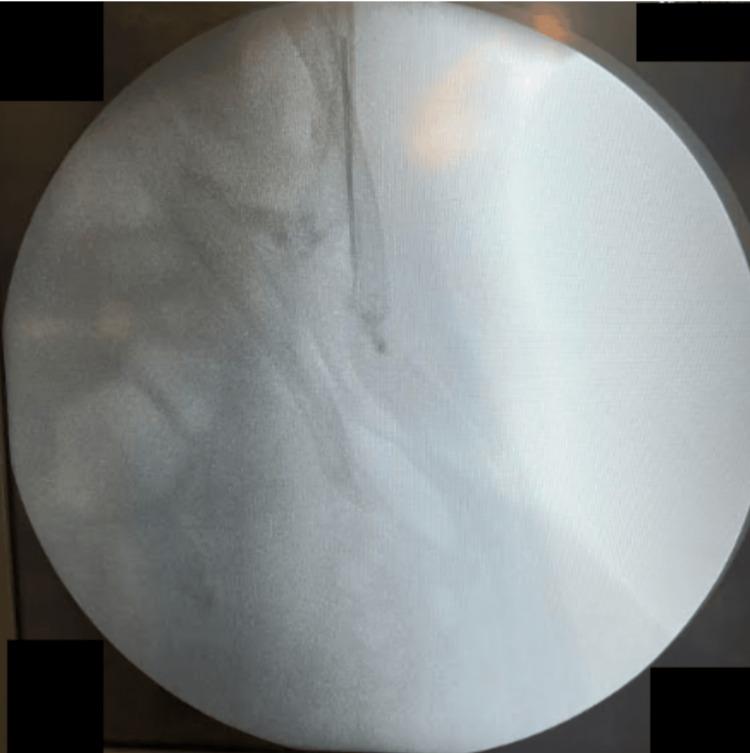

Midline laparotomy remains essential in gynecological oncology, and rectus sheath catheters (RSCs) are commonly used for postoperative analgesia. We report the case of a 46-year-old woman who underwent midline laparotomy for a suspected ovarian mass, which intraoperatively revealed mucinous ascites consistent with pseudomyxoma peritonei. An RSC was placed for pain control; however, during removal, a 5 cm segment remained embedded in the subrectus sheath. Initial imaging with plain X-ray failed to detect the retained catheter, which was eventually confirmed by computed tomography (CT). Intraoperative localization attempts using C-arm fluoroscopy and palpation were unsuccessful. A novel adjunctive approach using a Flir One Pro smartphone-based thermal camera (Flir One Pro Systems, Sweden), approved by clinical governance and operated by a trained surgeon, successfully identified localized heat on the abdominal wall, corresponding to inflammation caused by the retained catheter. Guided by this finding, a 2 cm incision was made to retrieve the coiled catheter without complications. The patient recovered well and was discharged on the third postoperative day. Histopathology confirmed pseudomyxoma peritonei, and the case was referred to a colorectal multidisciplinary team. This report highlights the feasibility and clinical value of thermal imaging as a radiation-free, real-time adjunct for detecting retained surgical materials, particularly when conventional imaging fails. Thermal imaging offers portability, precision, and safety, though its broader adoption requires standardized training, validation, and further research.

中线剖腹术在妇科肿瘤学中仍然至关重要,腹直肌鞘导管(RSCs)常用于术后镇痛。我们报告了一例46岁女性的病例,该患者因疑似卵巢肿块接受了中线剖腹术,术中发现黏液性腹水,符合腹膜假黏液瘤。放置了一根RSC用于控制疼痛;然而,在拔除过程中,一段5厘米长的导管仍嵌在腹直肌鞘内。最初的X线平片成像未能检测到残留导管,最终通过计算机断层扫描(CT)得以证实。使用C形臂荧光透视和触诊进行术中定位的尝试均未成功。一种新颖的辅助方法,使用经临床管理部门批准、由训练有素的外科医生操作的基于Flir One Pro智能手机的热成像相机(瑞典Flir One Pro系统公司),成功在腹壁上识别出局部发热,对应于残留导管引起的炎症。在此发现的引导下,做了一个2厘米的切口取出盘绕的导管,未出现并发症。患者恢复良好,术后第三天出院。组织病理学证实为腹膜假黏液瘤,该病例被转诊至结直肠多学科团队。本报告强调了热成像作为一种无辐射、实时辅助手段检测残留手术材料的可行性和临床价值,特别是在传统成像失败时。热成像具有便携性、精确性和安全性,不过其更广泛的应用需要标准化培训、验证和进一步研究。